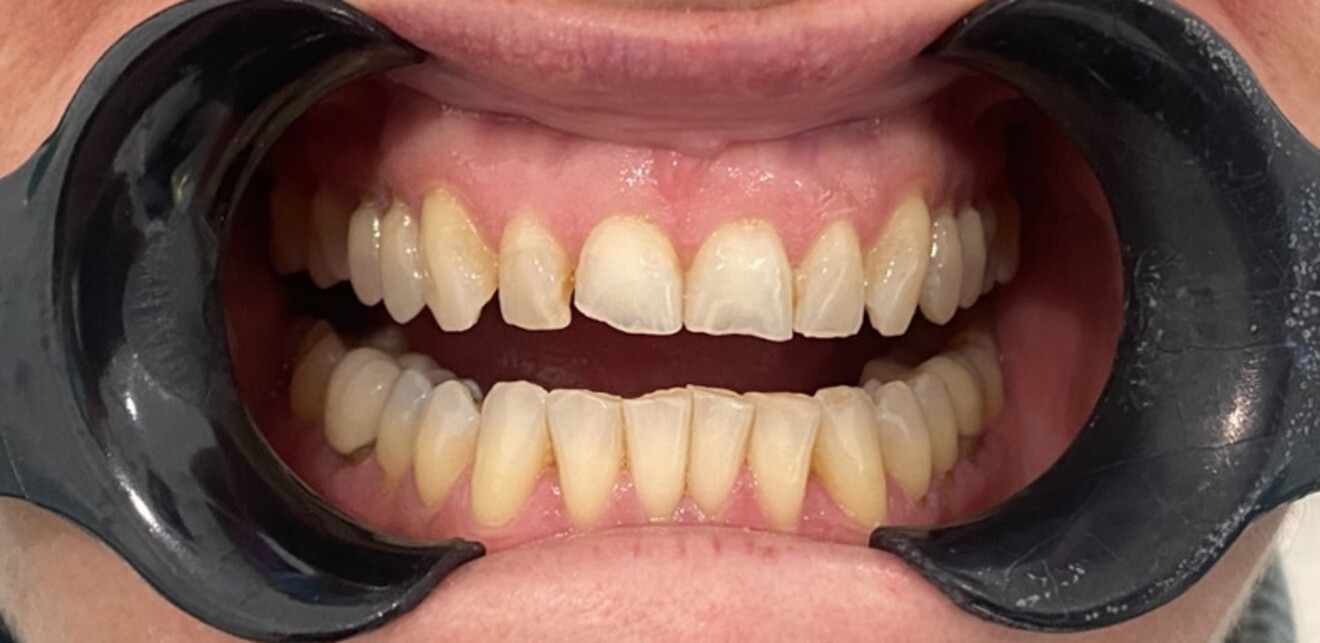

Figs. 5a & b: Still pre- (a) and posttreatment photographs (b) taken from the ClinCheck video—video integration into both orthodontic and restorative software allows for greater critical analysis and planning, including the full range of dynamic lip movements and gingival display characteristics to maximise position planning and aesthetic and functional outcomes.

Figs. 6a–e: Intra-oral post-treatment photographs.